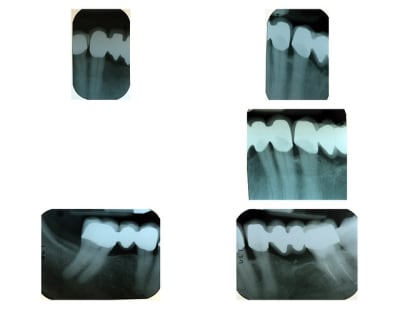

Zircone bridge p1 laahs1 - Eugenol

Ci-joint radio des bridge Zircone

Radio zirconia q5smv5 - Eugenol